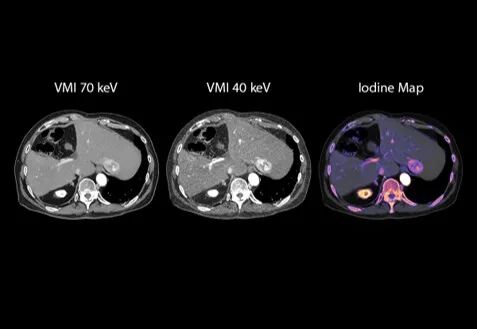

肝肿瘤

能谱成像,提供更多信息

🔹在肿瘤评估中,基于CZT-PCCT的能谱成像能力,可提供虚拟单能量图像及碘图等多维定量信息,有助于更清晰地呈现病灶强化特征与组织差异。相较传统成像方式,可以为肿瘤的检出、定性及评估提供更加丰富的影像参考。